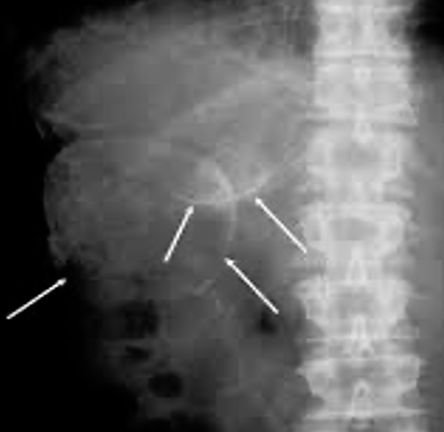

• plain x-ray can show the calcification in the wall of the cyst

Calcification in the wall of the hydatid cyst in the right lobe of the liver